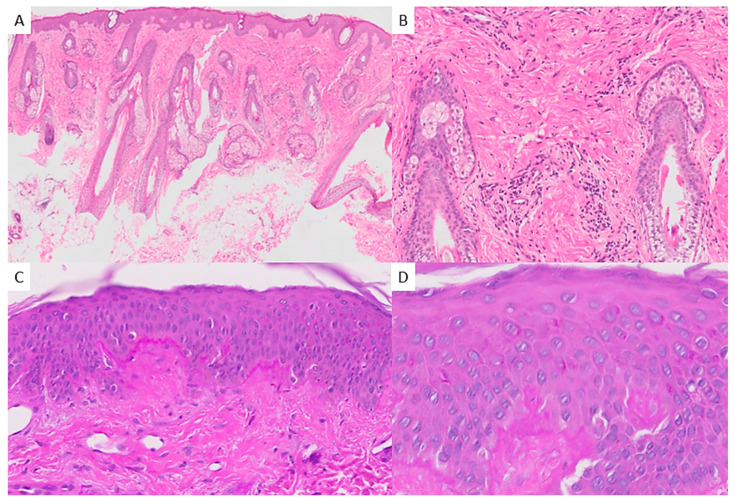

菊池-藤本氏病(KFD)是一种罕见的疾病,以坏死性淋巴结炎和发热为特征,通常与免疫失调有关。从组织学角度看,它的特点是坏死灶内有大量组织细胞和浆细胞树突状细胞,但明显缺乏中性粒细胞和嗜酸性粒细胞。最近的证据显示,儿童患者的发病率很高,与成人相比,他们可能表现出不同的特征。我们报告了一例 11 岁女孩的病例,她表现为持续发热、宫颈腺病和腮腺皮疹,经淋巴结活检后诊断为 KFD,活检结果显示淋巴结非化脓性坏死和组织细胞浸润。使用抗病毒药物和抗生素进行经验性治疗无效,但皮质类固醇治疗使症状得到缓解。文献综述发现了 48 项相关研究,涉及 386 个儿科病例,其组织病理学结果与 KFD 的经典描述一致。据报道,11.14%的病例有皮肤受累,从斑丘疹到红斑狼疮样糜烂不等。值得注意的并发症包括系统性红斑狼疮、斯约格伦综合征,以及罕见的嗜血细胞综合征或中枢神经系统受累。考虑到小儿病例中皮肤表现的频率较高,在对发热和淋巴结病的小儿患者进行鉴别诊断时应考虑菊地-藤本氏病。皮肤活检可能有助于诊断菊池-藤本氏病,并提供有关未来患系统性红斑狼疮潜在风险的宝贵信息。

Kikuchi-Fujimoto disease (KFD) is a rare condition characterized by necrotizing lymphadenitis and fever, often associated with immune dysregulation. Histologically, it features necrotic foci with abundant histiocytes and plasmacytoid dendritic cells but notably lacks neutrophils and eosinophils. Recent evidence reveals a notable prevalence among pediatric patients, who may exhibit distinct features compared to adults. We reported the case of an 11-year-old girl presenting with persistent fever, cervical adenopathy, and a malar rash, leading to a diagnosis of KFD following lymph node biopsy, which revealed non-suppurative necrosis and histiocytic infiltration. Empirical treatment with antivirals and antibiotics was ineffective, but corticosteroid therapy achieved symptom remission. A literature review identified 48 relevant studies involving 386 pediatric cases, with histopathological findings consistent with classical descriptions of KFD. Cutaneous involvement was reported in 11.14% of cases, ranging from maculopapular rashes to lupus-like eruptions. Notable complications included the development of systemic lupus erythematous, Sjögren syndrome, and rare instances of hemophagocytic syndrome or central nervous system involvement. Kikuchi-Fujimoto disease should be considered in the differential diagnosis of pediatric patients presenting with fever and lymphadenopathy, taking into account a higher frequency of cutaneous manifestations in pediatric cases. A skin biopsy may be helpful in diagnosing KFD and provide valuable information regarding the potential risk of developing systemic lupus erythematosus in the future.